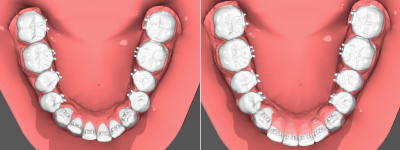

Un petit cas tout simple.

4 mois de traitement, Deux files et pour finir je vais faire deux aligneur sur le set up final ( technique ou l'on fait un aligneur de faible rigidité suivit d'un plus rigide ) .

Cout du matériel bracket/ set up imprimée / aligneur en dessous de 100$ .

Et un cas commencé par un généraliste dans mon hopital.

Celuis présenté en début de fil avec le patient edge to edeg.

Ici je n'ai strictement rien fait même pas controler la position des bracket sur le modéle en plâtre ou aider pour plier le fil.

Pas de set up 3D imprimé pour ce cas.

Juste indiquer de commencer par aligner le haut pour creer un overjet.

Un mois avec les bague et bonne proclination alignement .

La photo initial n'est pas la mienne je précise.

Comme d'hab la patiente ( une assistante ) ne sens rien et n'a aucun problème pour parler.